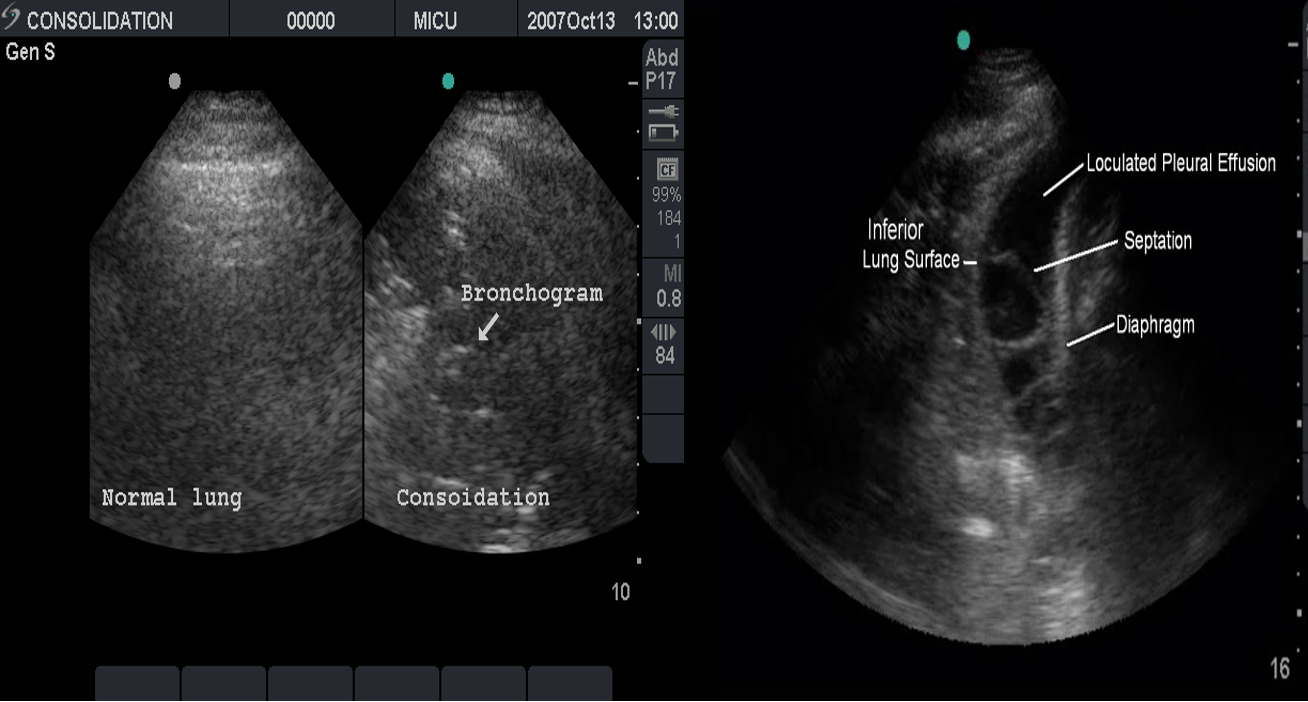

Ultrasound:

This is most useful if a pleural effusion is suspected on CXR. It can differentiate between clear fluid and fibrino-purulent effusions.

Air Bronchogram

Normally, it is not possible to identify air in bronchi within normally aerated lung, because the walls of the normal bronchi are too thin and air-filled bronchi are surrounded by air in the alveoli. However, if the alveoli are filled with fluid, the air in the bronchi contrasts with the fluid in the adjacent lung.